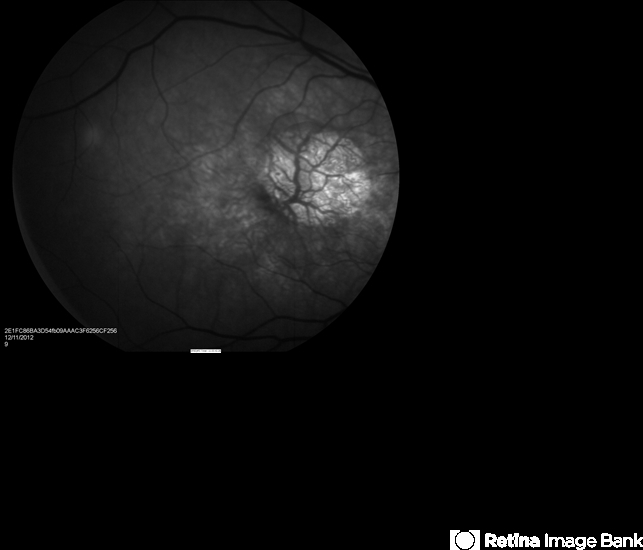

- geographic atrophy, advanced geographic atrophy, macula lesion, atrophic scar, atrophic spot, pigment epithelial atrophy, red-free, window defect

- Age related macular degeneration.